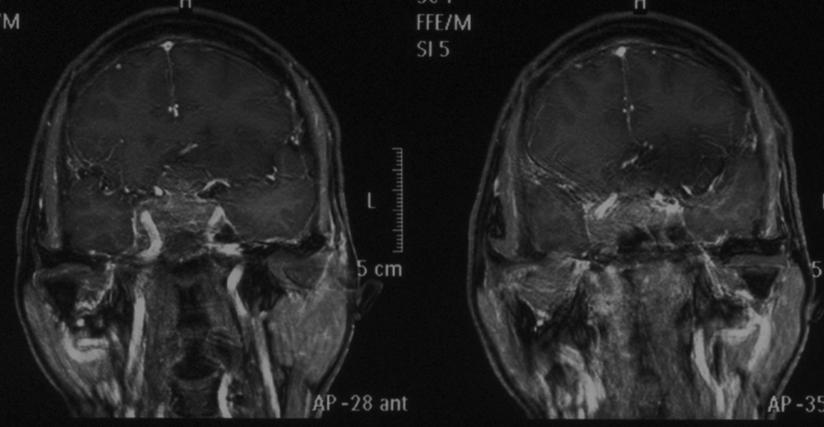

辽阳二院成功实施我市首例鼻内镜下经鼻腔蝶窦入路垂体瘤切除术

病例分享 经鼻蝶内镜分期切除巨大垂体腺瘤一例 神经内镜系列十九 浙二神外周刊 第277期 肿瘤